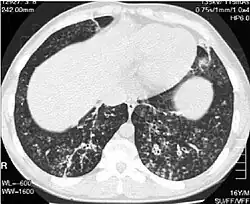

O diagnóstico da panbronquiolite difusa requer a análise dos tecidos do pulmão e dos bronquíolos, o que pode exigir uma biópsia ou uma tomografia computadorizada (TC) de alta resolução dos pulmões. Os critérios diagnósticos incluem inflamação grave em todas as camadas da bronquíolos respiratórios e lesões do tecido pulmonar que aparecem como nódulos dentro do bronquíolo terminal e respiratório em ambos os pulmões. Os nódulos na panbronquiolite aparecem como caroços opacos quando vistos em radiografias do pulmão e podem causar obstrução das vias aéreas, o que é avaliado por um teste de função pulmonar. A radiografia de tórax também pode revelar dilatação das passagens bronquiolares, outro sinal da doença. A tomografia mostra frequentemente bloqueios de algumas passagens bronquiolares por muco, que é referido como padrão em "árvore em brotamento". A hipoxemia, outro sinal de insuficiência respiratória, é revelada através da medição do conteúdo de oxigênio e dióxido de carbono do sangue, usando um exame de sangue chamado de gasometria arterial. Outros achados observados na panbronquiolite incluem a proliferação de linfócitos (glóbulos brancos que combatem as infecções), neutrófilos e histiócitos espumosos (macrófagos teciduais) no lúmen do pulmão. Bactérias como H. influenzae e P. aeruginosa são também detectáveis, com a última se tornando mais proeminente com a progressão da doença. O nível de glóbulos brancos, bactérias e outros conteúdos celulares do sangue podem ser medidos através de um hemograma completo. Níveis elevados de IgG e IgA (classes de imunoglobulinas) pode ser vistos, bem como a presença de fator reumatoide (um indicador de auto-imunidade). Hemaglutinação, uma aglomeração de células vermelhas do sangue em resposta à presença de anticorpos no sangue, pode também ocorrer. Neutrófilos, beta-defensinas, leucotrienos e quimiocinas também pode ser detectados no fluido do lavado broncoalveolar injetado então removido das vias aéreas bronquiolar de indivíduos com a doença, para avaliação.